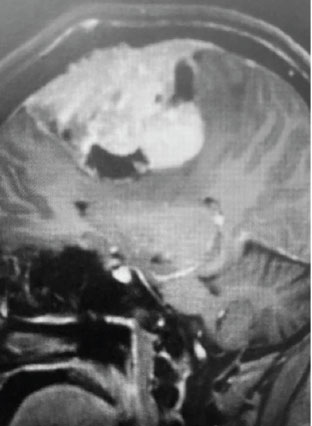

Fig 2. A) Post-operative, post-contrast, sagittal MRI.

Treatment: Given the size and location of this tumor, the best treatment was surgical removal. Surgery was performed by Dr. Michael Brisman. A craniotomy exposed the tumor along the convexity as well as the superior sagittal sinus. The tumor was removed, as was the involved convexity dura and the affected segment of the sagittal sinus. Removed dura and skull were replaced with duraplasty (with artificial dura) and a titanium mesh cranioplasty.

Outcome: The patient did very well and made a full recovery.